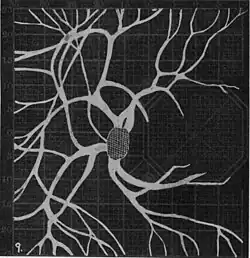

20. Venous engorgement. 21. After pressure over internal 22. Same case, normal. 23. Scotoma after ligation of common carotid. 24. Edematous swelling of nerve and retina. 25, Normal blind spot of other eye. -

Widening of angioscotoma under various conditions (holding head lower than trunk; holding the breath; making digital pressure on the same eye; (a vein) on opposite eye; (an artery) on opposite eye).